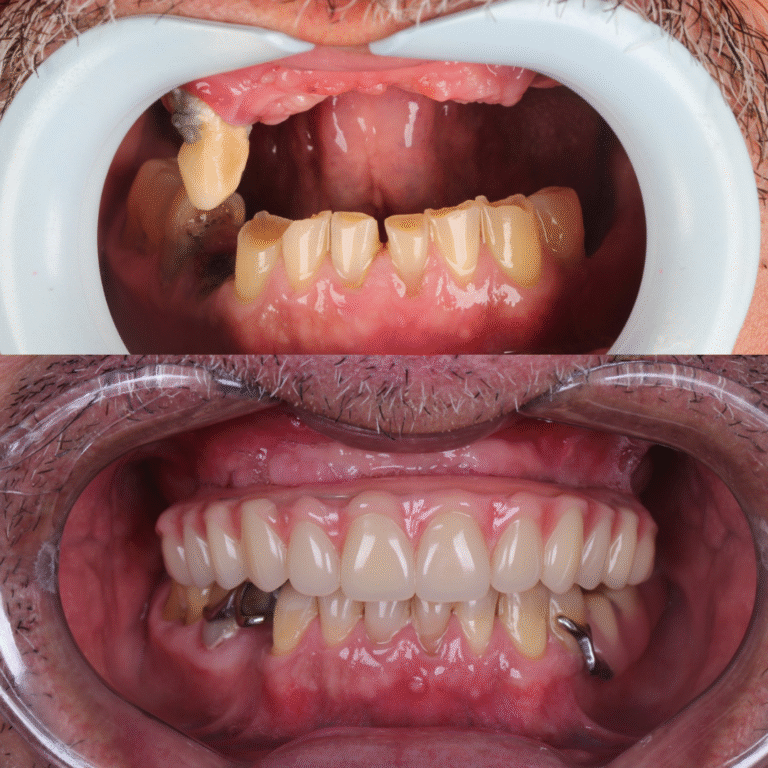

Veja alguns dos resultados obtidos através dos nossos tratamentos especializados.